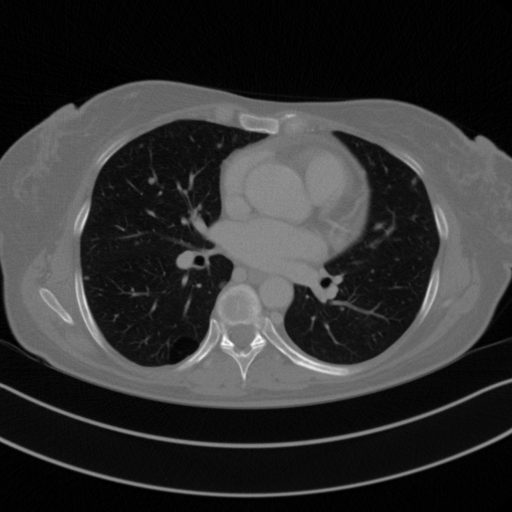

Image Grid

4×3 grid: Rows show different image types (Original NATIVE, Reconstructed NATIVE, Original VENOUS, Generated VENOUS), Columns show windowing techniques (No Window, Lung Window, Mediastinum Window)

Original NATIVE CT scan (input)

Lung window (WL -600, WW 1500 → Low −1350, High +150)

Reconstructed NATIVE CT scan (cycle consistency)

Lung window (WL -600, WW 1500 → Low −1350, High +150)

Original VENOUS CT scan

Lung window (WL -600, WW 1500 → Low −1350, High +150)

Generated VENOUS CT scan (A→B translation)

Lung window (WL -600, WW 1500 → Low −1350, High +150)

Windowing Parameters

- Lung Window: WL -600, WW 1500 → Low −1350, High +150 (optimal for pulmonary structures)